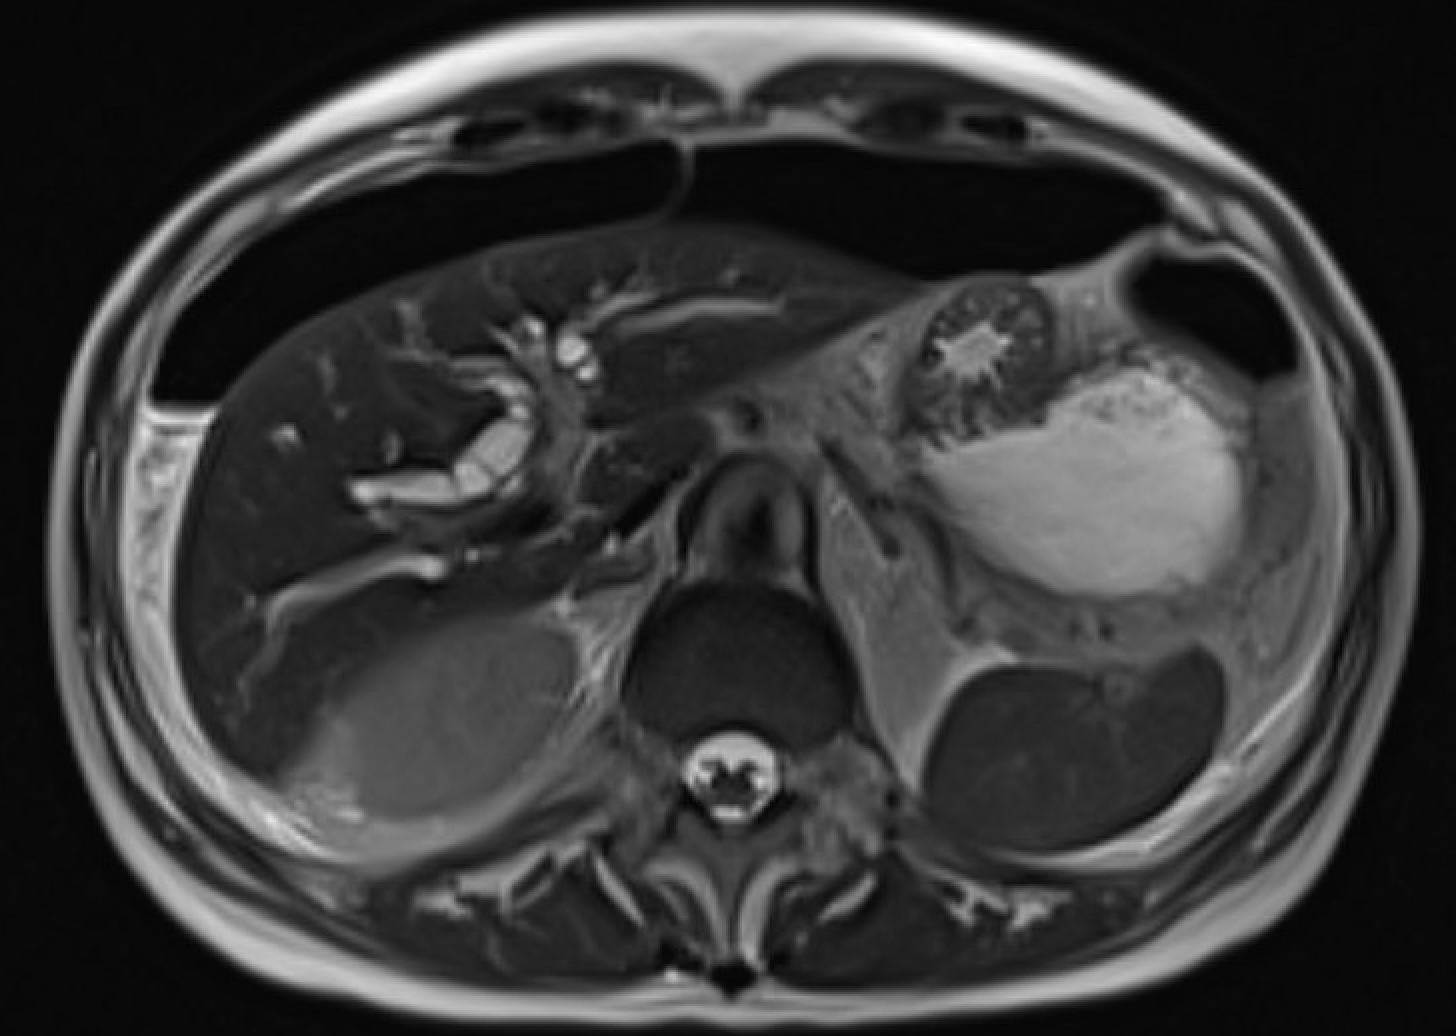

Hepatobiliary Emergencies

ConditionKey MRI FindingsTips

Spontaneous renal hemorrhage

(Wünderlich syndrome)

Subcapsular/perirenal T1-hyperintense collection with T2 signal heterogeneity. Subtraction images mandatory to exclude underlying enhancing neoplasm (AML, RCC most common causes)